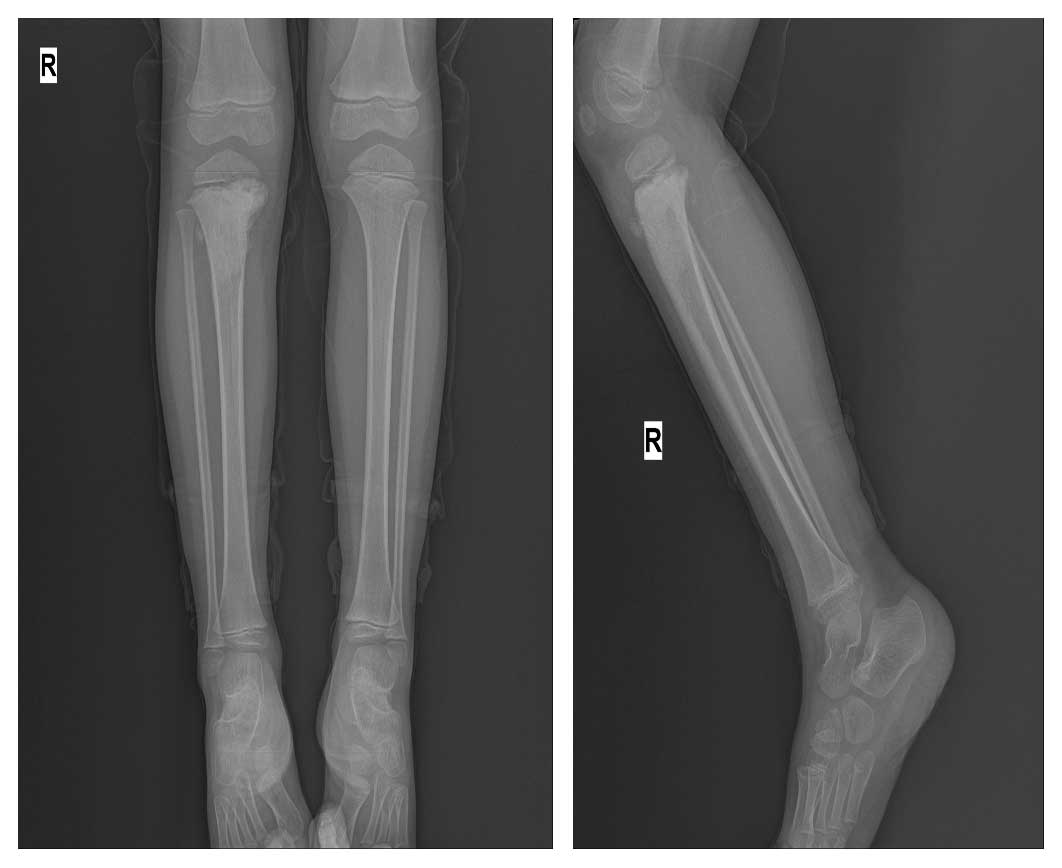

Ameliyat Öncesi: Röntgende proksimal tibiada düzensiz sınırlı sklerotik lezyon görülmekte.